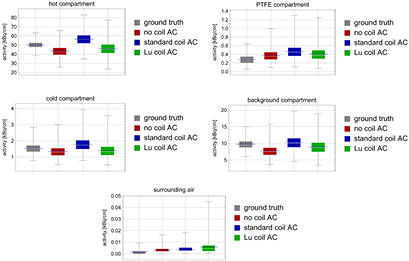

3.4. Phantom measurements

We computed the difference images between ground truth (image measured without coil and reconstructed without coil AC) and the images acquired with the Tx/Rx head coil and reconstructed them with different coil attenuation corrections (no coil AC, standard-coil-AC, and Lu-coil-AC). The reconstructed voxel size for all images was  and the difference images are shown in figure 11. As expected, the difference between ground truth and image acquired with the Tx/Rx head coil, but without coil AC, shows streaks due to uncorrected γ attenuation. Moreover, a negative bias of up 7 kBq

and the difference images are shown in figure 11. As expected, the difference between ground truth and image acquired with the Tx/Rx head coil, but without coil AC, shows streaks due to uncorrected γ attenuation. Moreover, a negative bias of up 7 kBq  (hot compartment VOI) was observed. When using the standard-coil-AC method, streaks due to γ attenuation by the coil are reduced, but a positive bias of up to 6 kBq

(hot compartment VOI) was observed. When using the standard-coil-AC method, streaks due to γ attenuation by the coil are reduced, but a positive bias of up to 6 kBq  (hot compartment VOI) is observed. When using the Lu-coil-AC method, streaks are further reduced but a negative bias is still present. However, the maximum bias is 4 kBq

(hot compartment VOI) is observed. When using the Lu-coil-AC method, streaks are further reduced but a negative bias is still present. However, the maximum bias is 4 kBq  , which is significantly smaller than for the other two cases.

, which is significantly smaller than for the other two cases.

Figure 11. Difference emission images of a single slice of the three compartment phantom. Left: Difference between ground truth and image without coil AC. Middle: Difference between ground truth and image with standard-coil-AC. Right: Difference between ground truth and image with Lu-coil-AC. Ground truth is data acquisition without coil and reconstruction without coil AC.

Standard image High-resolution imageAnalysis of the volumes of interest showed that, except for the VOI in the surrounding air and the background compartment, the mean activity concentration for the Lu-coil-AC best approaches the mean activity concentration of the ground truth. Mean values obtained using the standard-coil-AC always overestimated the ground truth values. Without coil AC, the activity concentrations in the hot, cold, and background compartment were underestimated, whereas the activity concentrations in the PTFE compartment and the surrounding air were overestimated. Standard deviation and coefficient of variation were highest for Lu-coil-AC, which was expected because of the low 176Lu activity. Mean values, differences of mean values to the ground truth, standard deviation and coefficient of variation for all VOIs and all 4 reconstructions are given in table 3. Corresponding Box–Whisker plots are shown in figure 12.

Figure 12. Box–Whisker plots for all 5 VOIs and ground truth, no coil AC, standard-coil-AC and Lu-coil-AC. Blue centre lines represent the mean of all voxel values, rectangles represent interquartile range of all voxel values, whiskers with fences represent minimum and maximum of all voxel values. The standard mean error was, in all cases, smaller than 1.26% of the corresponding mean value.

Image reconstruction for emission scans acquired with a Tx/Rx head coil but without any coil AC is not acceptable for the coil used in MR-BrainPET studies, since streak artefacts appear and a strong negative bias in the activity concentration is introduced (see difference images 11). Reconstruction with the standard-coil-AC leads to a generally positive bias, which is most probably due to cross-calibration between the well counter, the MR-BrainPET, and the ECAT Exact HR + PET scanner in order to achieve comparable quantitative images from both PET scanners. Reconstruction with the Lu ACF values leads to negative bias values for the activity concentrations, which are, however, significantly smaller than in both other cases. These residual biases may be either due to the missing energy extrapolation or to the fact that the cross-calibration for the standard-coil-AC was also used for the reconstruction with Lu-coil-AC. A further possible reason may be different scatter fraction for transmissions with 202 keV and 307 keV photons when compared to transmissions with 511 keV photons.

Neither the difference image for the reconstruction of the phantom data (figure 11) with standard-coil-AC nor the one for the reconstruction of the phantom data with Lu-coil-AC showed strong streak artefacts. In particular, no additional artefacts due to scattered gamma photons during measurement of the ACFs could be observed in these images, although the 3D acquisition of ACFs potentially leads to increased scatter contamination of the ACFs and equation (4) is not accounting for this effect. However, 2D acquisition of ACFs for minimised scatter contribution is not possible with the Siemens 3T MR-BrainPET scanner. We are currently working on using prior information and regularisation for the reconstruction of AC-maps from incomplete data for obtaining unbiased and artefact-free AC-maps, which still remains a challenge and is certainly beyond the scope of this work.

The reproduced activity concentration in the different VOIs of the three compartment phantom was altogether best for the Lu-coil-AC reconstruction, although it was not the closest to the ground truth for all VOIs. The magnitude of the observed bias without attenuation correction agrees with values reported in Eldib et al (2012b). The image noise for 176Lu based correction is slightly increased compared to all other cases (ground truth, standard-coil-AC, no coil AC) because of the very low intrinsic 176Lu activity. However, the increased image noise is barely noticeable in the patient/volunteer images; whereas the streak artefacts, which are noticeable in the images with standard-coil-AC, could be reduced by using the Lu-coil-AC. Since the transmission AC map was acquired with 511 keV radiation, we attribute the residual streak artefacts in this case to a residual mis-positioning of the standard AC map, with respect to the true position of the coil and/or the different spatial resolutions of the MR-BrainPET and the ECAT Exact HR + PET scanner. For the Lu-coil-AC, we attribute the residual streak artefacts to the missing energy extrapolation of the ACF values and the usage of the transmission AC map for scatter correction.